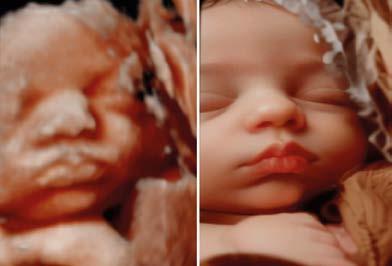

Van 3D/4D naar 6D: Een levensechte blik op jullie baby.

Wil je jouw baby écht zien zoals hij of zij eruit zal zien bij de geboorte? Met onze 3D- en 4D-echo’s krijg je al een heel realistisch beeld. Zijn of haar eerste glimlach, een geeuw of een duimpje in de mond. Het is alsof je echt al een glimp opvangt van hoe je kindje er echt uit komt te zien. Als je denkt dat dit realistische is! Dan gaan we nog een stap verder, want dankzij de nieuwste 6D-technologie ontvang je haarscherp en natuurlijk beeld waarin je kindje tot leven komt. Een onvergetelijke ervaring die je voor altijd bij je draagt!

Pretecho’s: een persoonlijke herinnering

Pretecho’s zijn niet-medische echo’s die je op eigen verzoek kunt laten doen wanneer jij dat wilt. Ze hebben als doel om ouders een extra moment te geven om hun baby te bewonderen, vaak in 2D, 3D of 4D beeld. Deze echo’s kunnen op elk moment in de zwangerschap worden uitgevoerd, maar bieden geen medische informatie over de baby.

Veel ouders kiezen voor een pretecho om achter het geslacht van het kindje te komen of om samen met eventueel aanstaande broertjes/zusjes en opa’s/oma’s de baby in een ontspannen sfeer te bewonderen en herinneringen te maken. De 3D/4D echo is vooral geliefd, omdat deze een gedetailleerd beeld van het gezichtje van de baby geeft. Soms zie je de baby zelfs lachen of gapen! Dit kan helpen om een nog sterkere band met je baby te voelen. Hoewel pretecho’s geen medische functie hebben, kunnen ze bijdragen aan een bijzondere ervaring tijdens de zwangerschap.